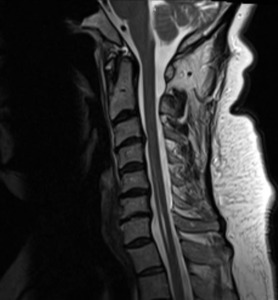

A second MRI examination of the cervical spine without contrast was ordered approximately 1 year following the accident due to persistent and worsening symptoms. This was necessary to evaluate radiculopathy and to rule out enlargement of syringohydromyelia. The syringohydromyelia at the cervical and upper thoracic cord was unchanged compared to a study 6 months prior. Annular tear, mild posterior disc bulging and mild disc degeneration were present at C3-C4. Mild bulging and degeneration was present at the C5-C6 disc with Luschka joint osteophytes and severe foraminal stenosis at C6 on the right. Severe disc degeneration was evident at C6-C7 with mild disc bulging and severe bilateral bony foraminal stenosis at C7. There was no evidence of Chiari malformation, tumor, or other congenital anomalies. (See Figures 1-4)

She was diagnosed with traumatically-induced cervical radiculopathy, cervical spine segmental dysfunction, and syringohydromyelia at the cervical and upper thoracic cord. Pre-existing disc degeneration and osteophytes at the cervical spine may have predisposed her to this condition.